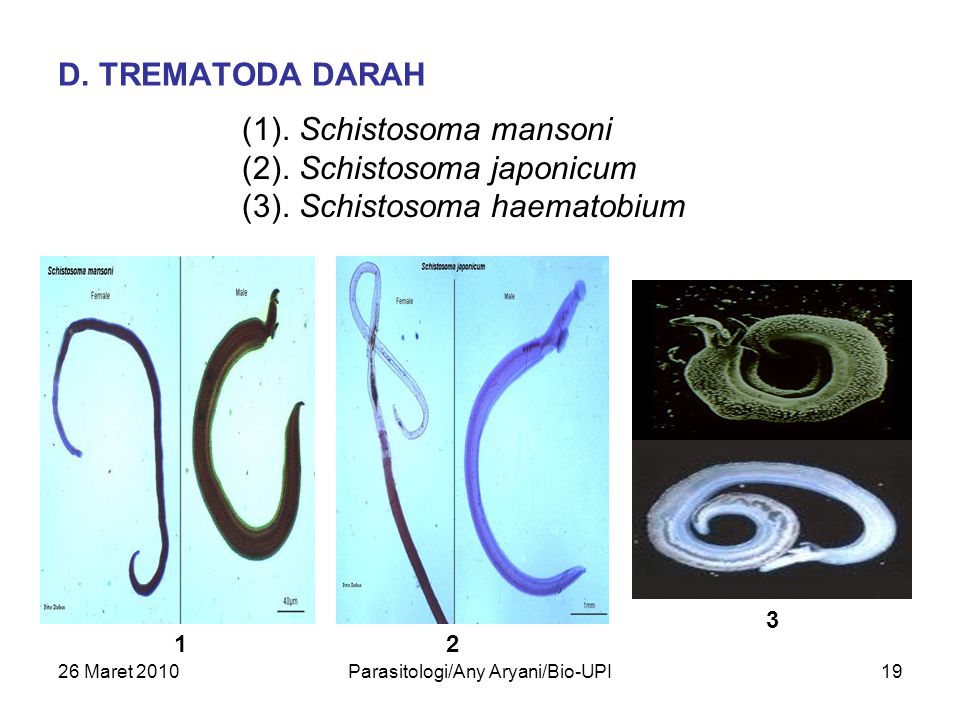

Шистосомоз: что нужно знать о паразитах